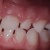

Piimahammaste kulumise häired

Igal kolmandal lapsel on piimahambad kulunud kas peetunult ebaühtlaselt või patoloogiliselt Kuidas see mõjutab jäävhammaste ...